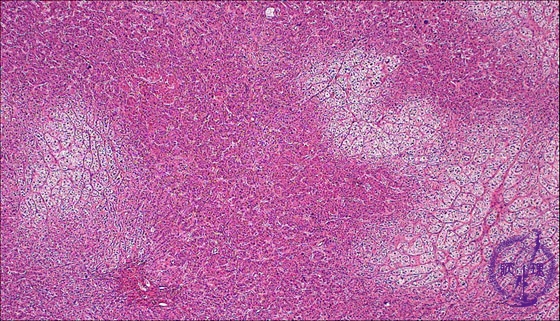

• š(13)Adrenocortical adenoma (Cushing syndrome)

Microscopic findings (HE stain, low power view). The tumor is composed of both clear and eosinophilic cell components.